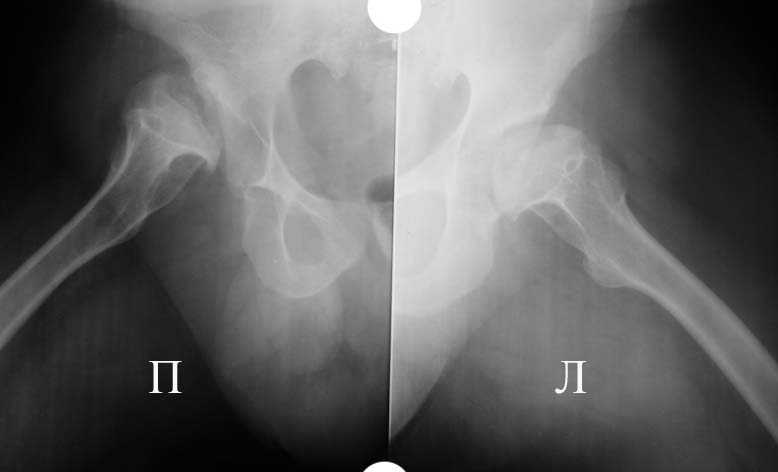

Аксиальная проэкция обоих т/б суставов